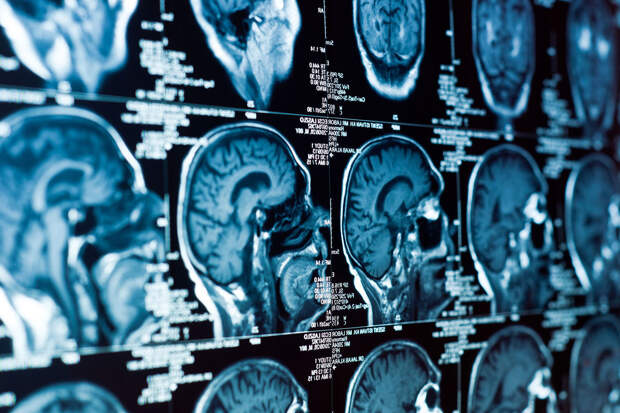

Исследователи из Цюрихского и Нью-Йоркского университетов представили технологию, которая позволяет одновременно и с высокой точностью стимулировать несколько участков мозга с помощью ультразвука. Работа опубликована в журнале Nature Biomedical Engineering (NBE).

Новый прибор, состоящий из сотен миниатюрных излучателей, формирует ультразвуковые импульсы, которые накладываются друг на друга подобно световым волнам в голограмме. Так в мозге возникают несколько фокусных точек, где активируются нейронные сети.По словам профессора Даниэля Разански, возглавившего проект, воздействие сразу на несколько зон позволяет использовать ультразвук меньшей интенсивности, что делает метод безопаснее. Ранее при слишком слабом воздействии стимуляция оказывалась бесполезной, а при чрезмерно сильном — затрагивала весь мозг и могла повредить ткани.

Технологию испытали на мышах: животным проводили неинвазивную стимуляцию через череп, фиксируя активность нейронных сетей. Ученые предполагают, что эффект ультразвука связан не только с легким локальным нагревом, но и с механическим воздействием на ионные каналы нейронов.

Сейчас метод находится на стадии фундаментальных исследований, но в перспективе может применяться для терапии болезни Альцгеймера, эпилепсии, тремора, болезни Паркинсона и депрессии.